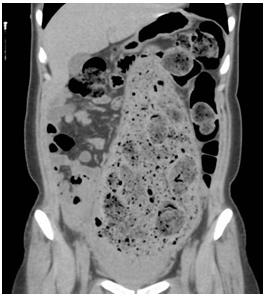

一个月前刚刚生产,与生产部位完全吻合的巨大粪便块。马上进行了腹部CT 检查。

照片6:腹部CT

乙状结肠出现明显扩张,2周的粪便镶嵌其中。乙状结肠上部将肝下方,胃和横结肠向上方挤压,左侧乙状结肠下方可确认内腔积蓄圆形粪便和气体。

通常,结肠直径超过10cm后压力差可能穿破肠壁。本病例中,结肠已经超负荷扩张。实际上,患者的肠道长时间扩张,因没有基础疾病,被诊断为慢性假性肠闭塞症。可能导致肠道肠肌神经丛或粘膜下神经丛的功能障碍。